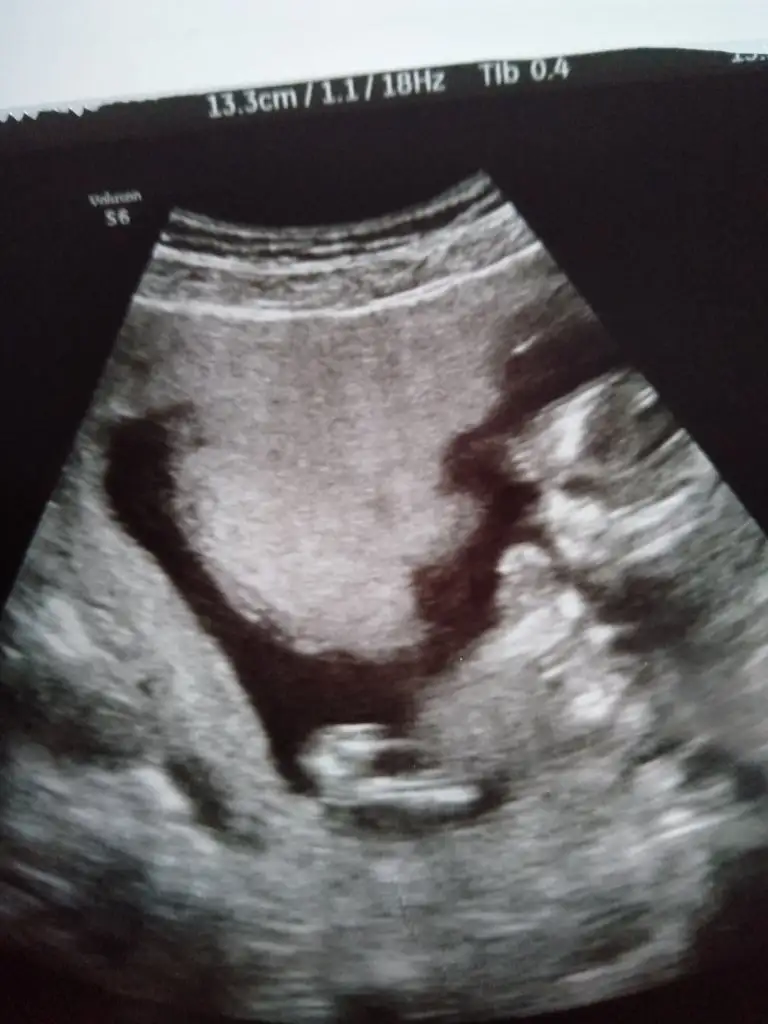

Erkek gibi sankiIkra meyra bir tahminde bulunabilir misiniz acaba. 13 haftalık ama ultrasonda 1 hafta önde gidiyor

Teşekkürler doktorda erkeğe benzetti ama pozisyon itibariyle çok net olamadi birdahaki ay kesin dediErkek gibi sanki

Net görüyormusunKız görünüyor

Diğer usg netti canım bence erkek diğer USG ileNet görüyormusun

Evet dik görünüyor erkekAçı paralel değil yani dimi , burada öle görünüyor